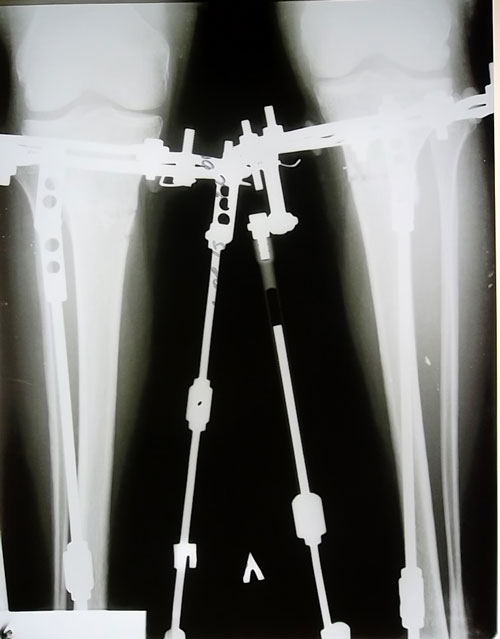

- Диагноз: о-образная деформация нижних конечностей

сегодня 78 день после ОП

снимки я свои видела -я бы хотела оценку к ним или какие-то комментарии,я могу ехать ?

Здравствуйте, Ягодка! Вы не переживайте, необходимо сделать компрессию (сжатие), для этого:

смотрите на фото!

1) трогаем только средний стержень, я его отметила на фото (для понятия о чём речь)

2) откручиваем внутреннюю гайку на этом стержне снизу (без разницы на сколько)

3) и начинаем работать с нижней гайкой: делаем пометку на ребре гайки ярким лаком для ногтей и пометку на ребре кольца так, чтобы они соприкасались в одном месте!

4) закручиваем нижнюю гайку на 360 градусов по ходу часовой стрелки

(полный оборот так, чтобы пометки соприкоснулись - это чтобы не сбиться) и таких полных 5 оборотов = 5 мм.

Высылаю рисунки для понятия, если что то непонятно сразу напишите.